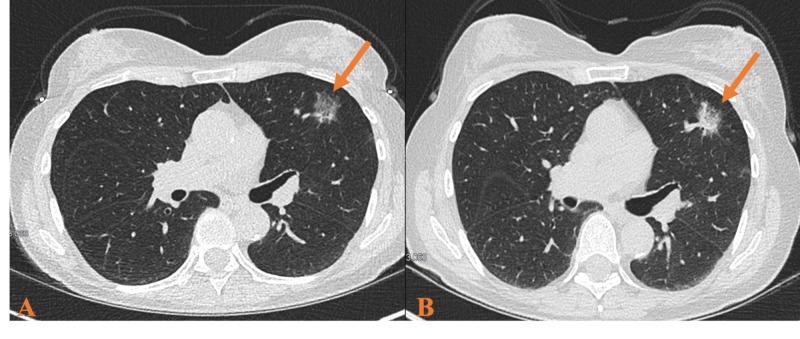

Lung cancer still remains one of the most common cancers throughout the world, especially in smokers. Adenocarcinoma is now the predominant histological type in many western countries. The etiology of adenocarcinoma is unknown, but evidence suggests that atypical adenomatous hyperplasia (AAH) may act as a precursor lesion. Here we present two case reports of patients diagnosed with AAH on biopsy, highlighting 1) available treatment strategies and 2) AAH's progression to adenocarcinoma. A review of AAH is warranted as little literature is currently available regarding its treatment strategies, especially in light of its role as a precursor to adenocarcinoma. In this review, we will address the following topics: 1. What is the pathophysiology of AAH? 2. What is the natural history of AAH and its risk of malignant transformation? 3. When is surgery recommended? 4. What is the role of stereotactic body radiotherapy (SBRT) in the rare patient who refuses surgery?